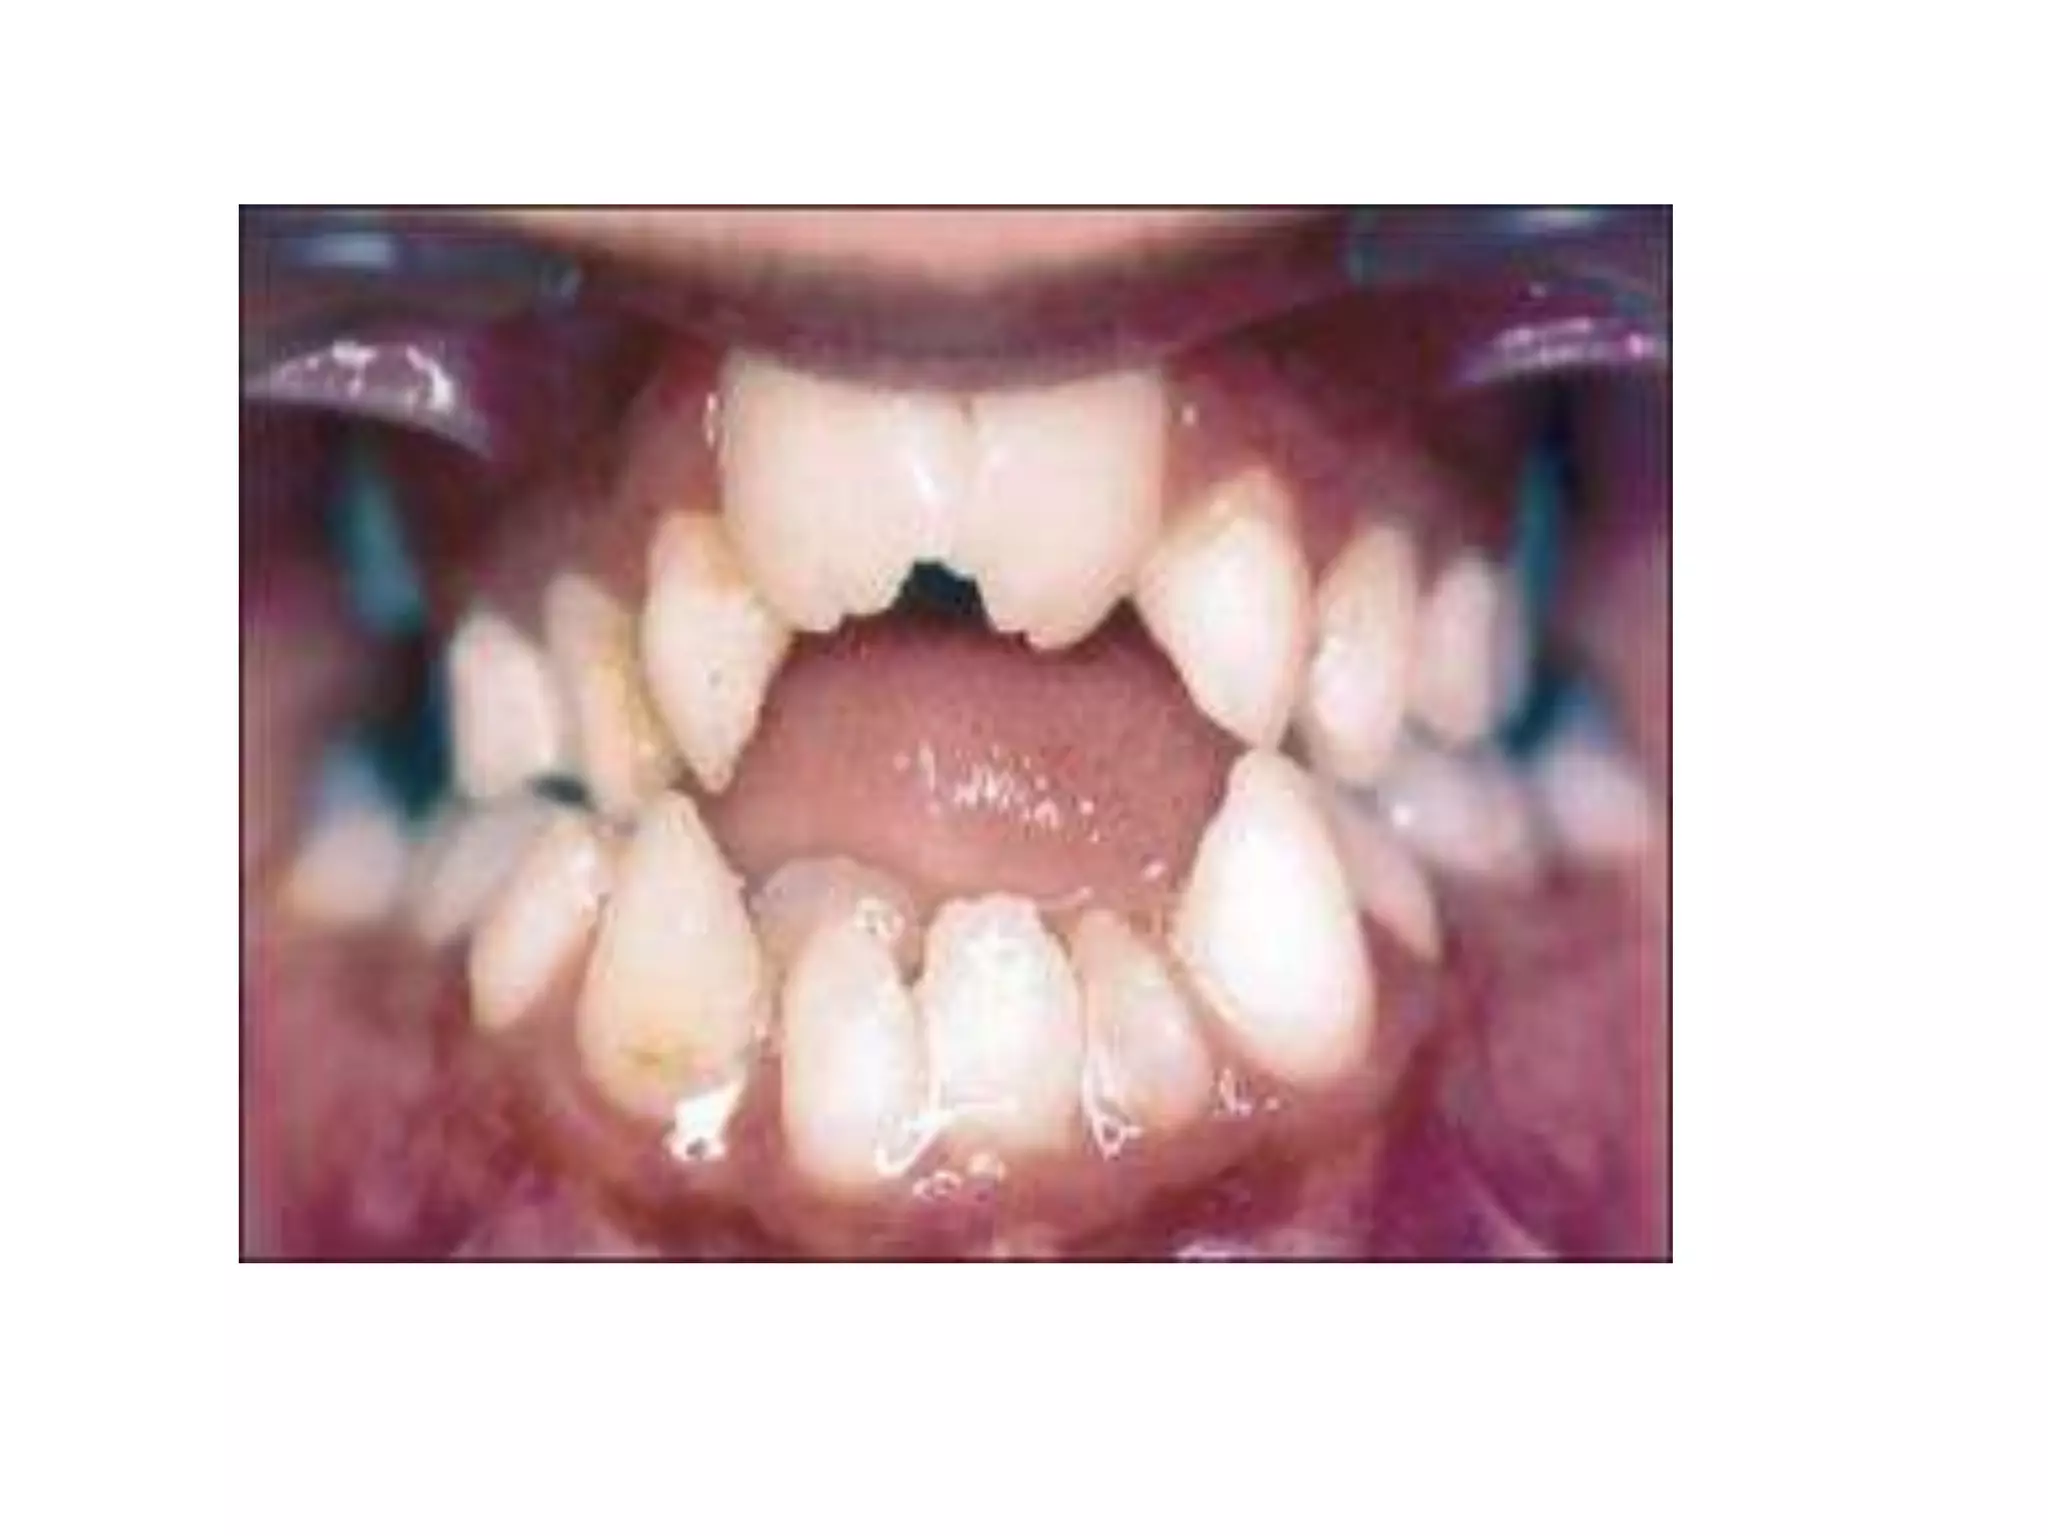

Dentinogenesis imperfecta (crumbling teeth)

Mutilation (gnawing the ends of teeth)

OSTEOGENESIS IMPERFECTA (BRITTLE BONES) Commonestgenetic disorder of bone Type 1 collagen (abnormal synthesis & structure) Abnormalities of bones, teeth, sclerae and skin c/f: Osteopenia Liability to fracture Laxity of ligaments Blue sclerae Dentinogenesis imperfecta (crumbling teeth)

Congenital hyperuricaemia (Lesch-Nyhan syndrome) •Rare x-linked recessive • Absence of enzyme hypoxanthine guanine phospho ribosyl transferase (HGPRT) • Results in excessive uric acid and gout • c/f: • Young boys mental retardation and prone to self Mutilation (gnawing the ends of teeth) Mild cases with severe gout.